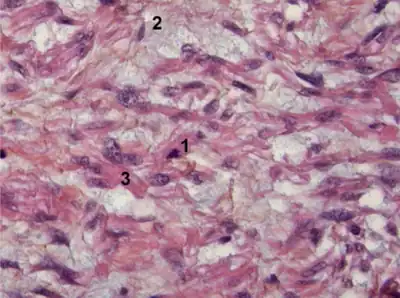

Myxoid leiomyosarcoma of bladder- 1) Abnormal mitosis 2) differentiated leiomyosarcoma 3) pools of hyaluronic acid

Myxoid leiomyosarcoma of bladder- 1) Abnormal mitosis 2) differentiated leiomyosarcoma 3) pools of hyaluronic acid Histopathology of leiomyosarcoma shows variable atypia, often with cytoplasmic vacuoles at both ends of nuclei, and frequent mitoses.[11]

Histopathology of leiomyosarcoma shows variable atypia, often with cytoplasmic vacuoles at both ends of nuclei, and frequent mitoses.[11]